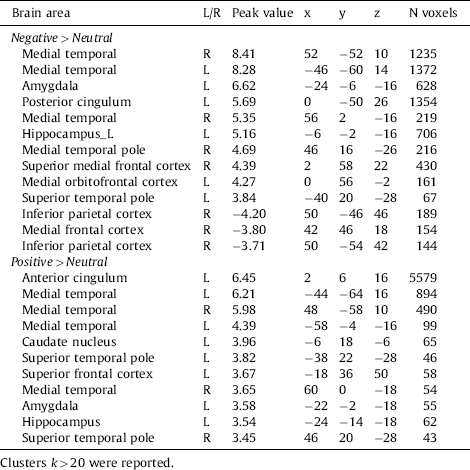

Brain areas involved in emotional processing were activated by the task, in both the Negative minus Neutral contrast and the Positive minus Neutral contrast, see Table 3 and Fig. 2. For the Negative minus Neutral contrast and the Positive minus Neutral contrast, these regions included the amygdala, hippocampus and orbitofrontal cortex.

Table 3 Whole-brain activation within subjects during the negative and positive contrast.

Fig. 2 Brain activation during the Negative minus Neutral contrast, showing the task effect. P < .05, FWE-corrected.